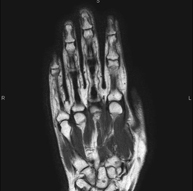

- RM Mano / dedos

Exploración para el estudio de lesiones en tendones, ligamentos y pequeñas articulaciones. Es la prueba que mejor permite diagnosticar las frecuentes capsulitis por traumatismo, la artrosis y las roturas de tendones. Tiene una duración aproximada de 20 minutos. No emplea radiación ionizante.